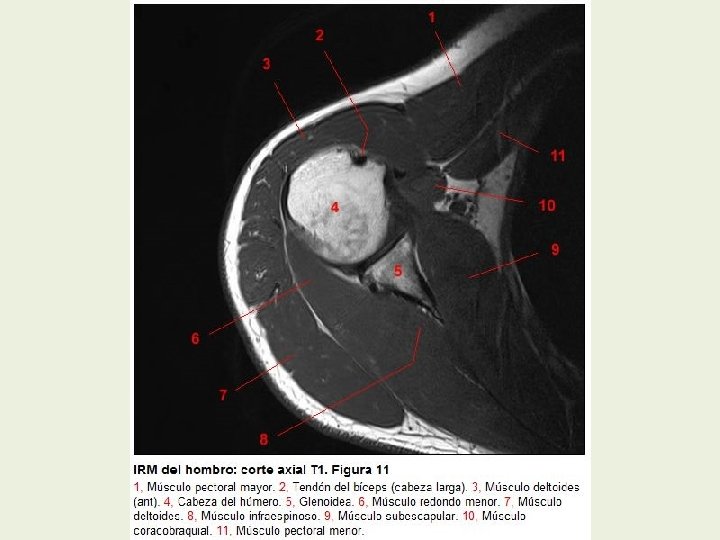

Hombro Cortes axiales RMN